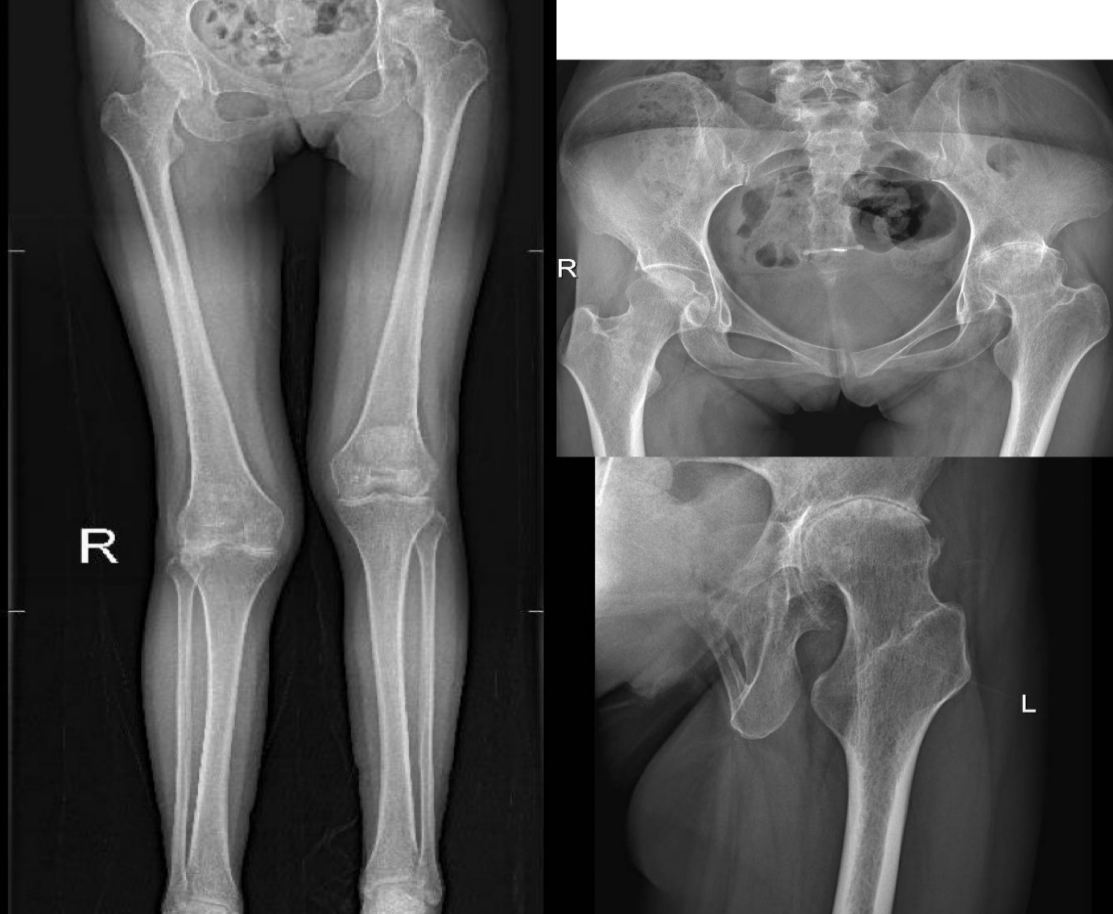

发病初期的关节表现为关节僵硬、肿胀、疼痛等,通常是从手指近段指间关节、掌指关节、手腕等小关节最先发病,逐渐表现为对称性多个关节受累,最终可有典型的关节炎症改变,如长时间晨僵、肿胀、疼痛等,最后可发生关节畸形,并丧失关节正常的功能。

经过严格规范的药物治疗后效果欠佳,且患者出现关节畸形,严重影响关节功能的情况,可考虑手术治疗,手术治疗具有矫正畸形、恢复关节功能的作用。手术方式包括:关节镜下手术、关节置换术等。